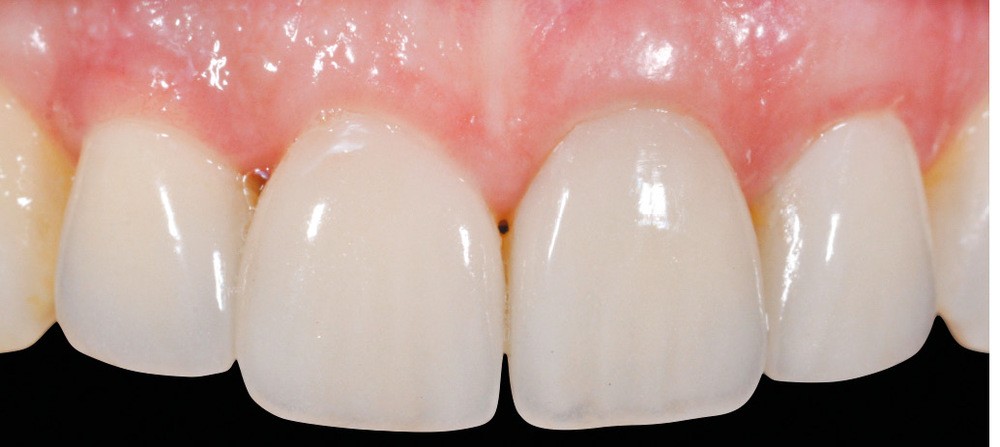

Il faut impérativement modérer l’enfouissement de limite de la couronne, particulièrement en proximal. Une limite juxta-gingivale facilite l’élimination des excès de colle. L’emploi de piliers conçus par CAO, et fabriqués par usinage en titane ou en zircone, est devenu courant et toutes les marques la proposent à l’heure actuelle.

Le prothésiste définit les formes de contour grâce à un logiciel de CFAO et usine la pièce lui-même, ou la commande à un tiers.